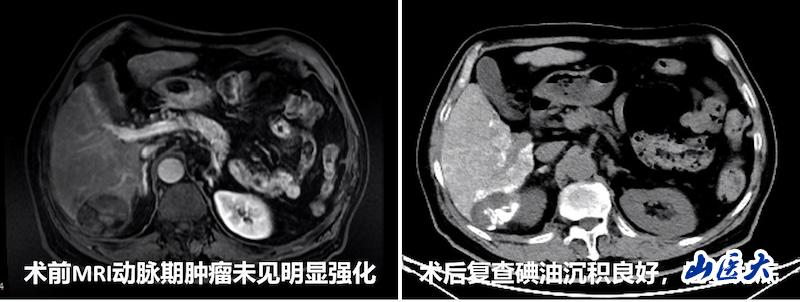

该患者为老年男性,影像资料显示为乏血供型肝癌,其供血血管细小复杂,传统介入手段面临较大挑战。第二医院介入治疗科团队经深入讨论,决定采用“CBCT三维成像引导技术”。科室负责人李强介绍,此技术能够通过三维重建肿瘤血供,精准识别毫米级滋养血管,实现“亚肝段”级精准栓塞,特别适用于常规经导管动脉化疗栓塞术(TACE)后复发、乏血供肝癌、多支供血肿瘤及需保留肝功能的患者。相比传统造影技术,CBCT三维成像引导技术不仅能缩短手术时间、减少患者辐射暴露,还能降低过量造影剂引发的肾功能损伤风险。

手术过程中,在CBCT的实时引导下,团队精准锁定患者肿瘤的三支供血动脉,并利用微导管逐一超选至目标血管,顺利完成化疗栓塞。栓塞后造影显示肿瘤血管完全消失,病灶碘油沉积良好。术后一周复查CT,碘油沉积范围与PET/CT提示的活性病灶范围完全一致,治疗效果明显。